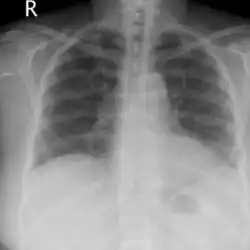

Lung auscultation may reveal abnormal breath sounds such as rhonchi (snoring-like) or crackles (rattling), and chest imaging can show lung consolidations[4] and edema.[5] Decreased lung volumes, including a reduction of average 0.7 liters in forced expiratory volume in 1 second and vital capacity, is found on spirometry. Laboratory studies do not show specific abnormalities, but low oxygen levels in blood, slightly elevated white blood cell count and lactate dehydrogenase levels may be seen.[1]